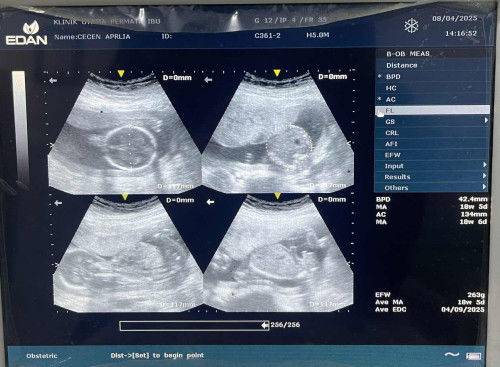

Sharing seputar usg

Mau nanya dong bun ini kalo hasil usg seperti ini fotonya normal ga ya bun umur janin menurut usg pertama seharusnya 17week 6day setelah USG ke 2 umur janin jadinya 18week 6day. Dokternya ga jelasin detail bun hanya bilang kepala leher pundak kaki dan tangan kemudian detak jantung bayi yg normal. Itu aja jdi saya kurang puas sama penjelasan dokternya